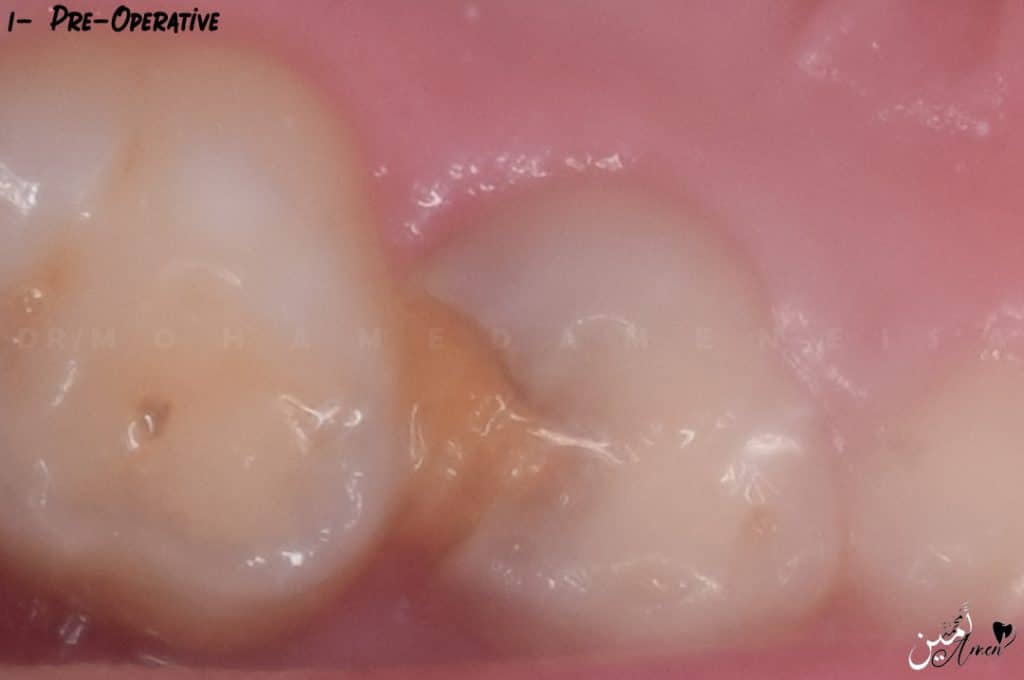

Of course, you must take a pre-operative x ray to confirm your diagnosis.